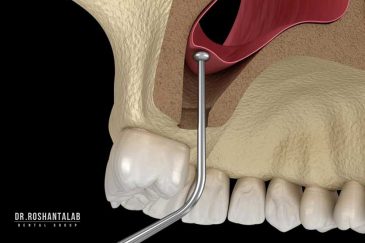

🔸کاشت ایمپلنت فلپ لس یا بدون جراحی و بدون بخیه زیر سه دقیقه

🔸جراحی پیشرفته نظیر سینوس لیفت